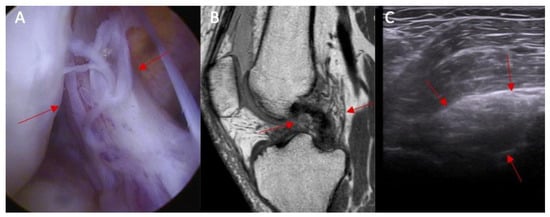

Figure 1.

Anatomical part of the study. (A) Ultrasound examination: point A—baseline point of the ACL in the ultrasound image before the application of force and point B—the same point after the application of force in the anterior drawer test. Section A–B—actual functional instability on ultrasound examination. Yellow lines indicate the inclination of ACL. (B) arthroscopy view— arrows indicate intersection of the ACL.

Figure 3.

The inclination of the ACL—the ultrasound view (ACL is marked with red arrows). (A) normal = 45 degrees angle between extension of posterior border of the ACL and base line and (B) abnormal < 40 degrees angle between extension of posterior border of the ACL and base line.

Figure 4.

(A) ACL tear confirmed in arthroscopy view and MRI examination; (B) (marked with red arrows); and (C) abnormal inclination of the ACL in ultrasound view.